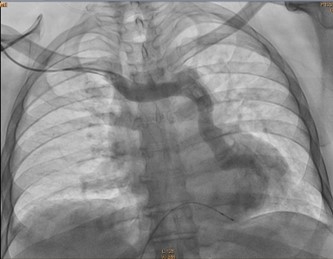

During the procedure in the cardiac catheterisation laboratory, difficulties were encountered in advancing the guidewire towards the subclavian vein. Consequently, bilateral subclavian vein angiography was performed, which revealed a persistent left superior vena cava with anomalous drainage into the coronary sinus. The procedure was therefore deferred.

A cardiac CT angiogram confirmed the diagnosis. The cardiothoracic surgery team was subsequently consulted, and an epicardial pacemaker was successfully implanted via a subxiphoid approach in DDDR mode.